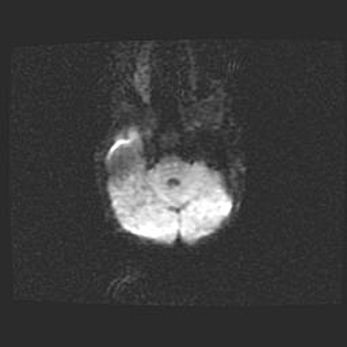

Сообщающаяся гидроцефалия. Кистозная энцефаломаляция головного мозга.

Возраст: 3 месяца 4 дня

Вес: 3100 г

Пол: женский

Окружность головы: 34 см

Срок гестации: 31 неделя

Кистозная энцефаломаляция головного мозга - одна из форм поражения головного мозга в детском возрасте. Характеризуется возникновением множественных и распространённых кист в коре, белом веществе и подкорковых образованиях головного мозга у плодов, новорождённых и детей раннего возраста. Развитие кистозной энцефаломаляции связано с внутриутробной асфиксией и гипотонией, родовой травмой, тромбозом синусов, пороками развития сосудов, инфекциями, сепсисом и другими причинами. Наиболее значимые инфекционные агенты: вирусы простого герпеса, цитомегалии, краснухи, токсоплазмы, энтеробактерии, золотистый стафилококк и другие.